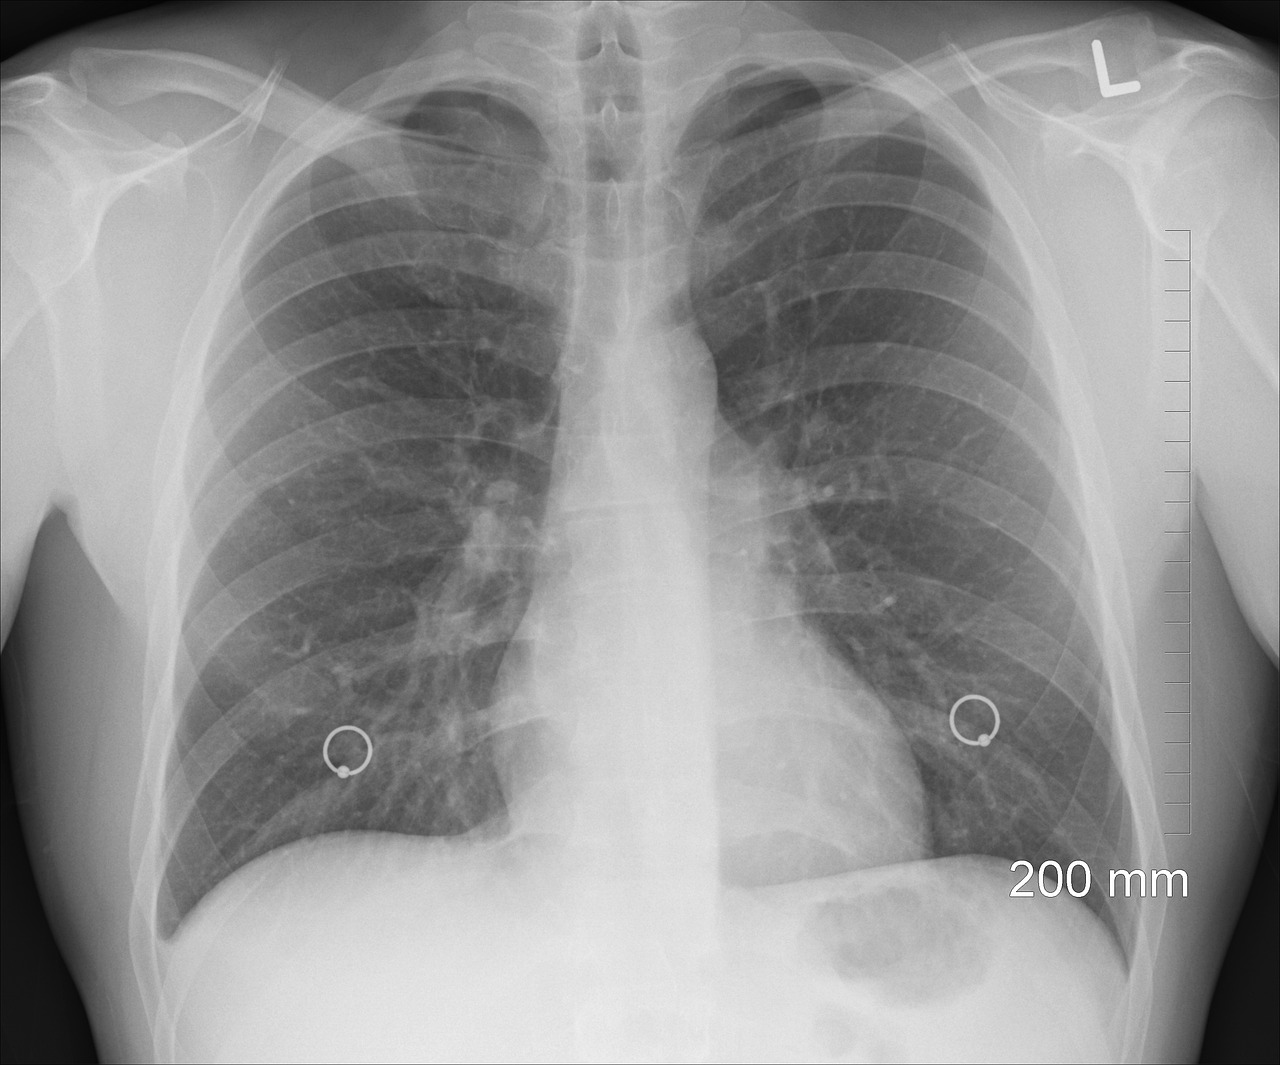

여정을 시작하기 위해 CF의 신비를 풀어보겠습니다. 선천성 낭포성 폐질환은 태어날 때 존재하는 질환들이 폐에 영향을 미쳐 낭종이나 액체로 가득 찬 주머니들을 형성하는 것을 말합니다. 이 낭종들은 정상적인 폐 기능을 방해하고 심각도가 다양하여 각 개인에게 독특한 도전 과제를 제시할 수 있습니다. 다양한 유형의 CF를 이해하는 것부터 잠재적인 원인을 탐구하는 것까지, 이 섹션은 상태에 대한 포괄적인 개요를 제공하여 더 깊은 이해를 위한 토대를 마련하는 것을 목표로 합니다.

주기적인 영상검사: 환자는 주기적인 영상검사 (CT 스캔, X-레이 등)를 받아 폐의 변화나 낭포 크기 등을 모니터링받아야 합니다.